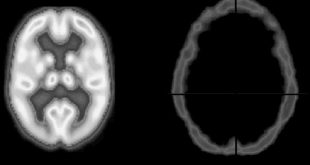

نوروسافاری | این مقاله قصد دارد توضیح مختصر اما مفیدی در مورد وضعیت های مختلف کما از جمله سندروم قفل شدگی، زندگی نباتی و مرگ مغزی فراهم آورد. در ادامه با ما همراه باشید. لازم به ذکر است که هر کدام از موارد اشاره داده شده در این نوشته تنها …